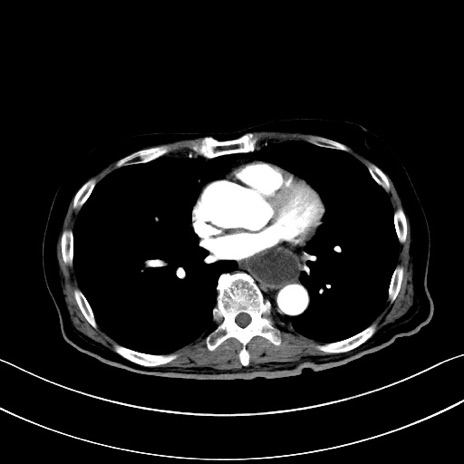

症例28(横断像)

【症例】60歳代男性

【主訴】嘔吐

【現病歴】胃癌にて胃全摘後。食思不振が悪化し、夜中に嘔吐することがある。

【既往歴】胃癌、胃全摘、脾摘、胆摘後

【データ】WBC 5900、CRP 10.56